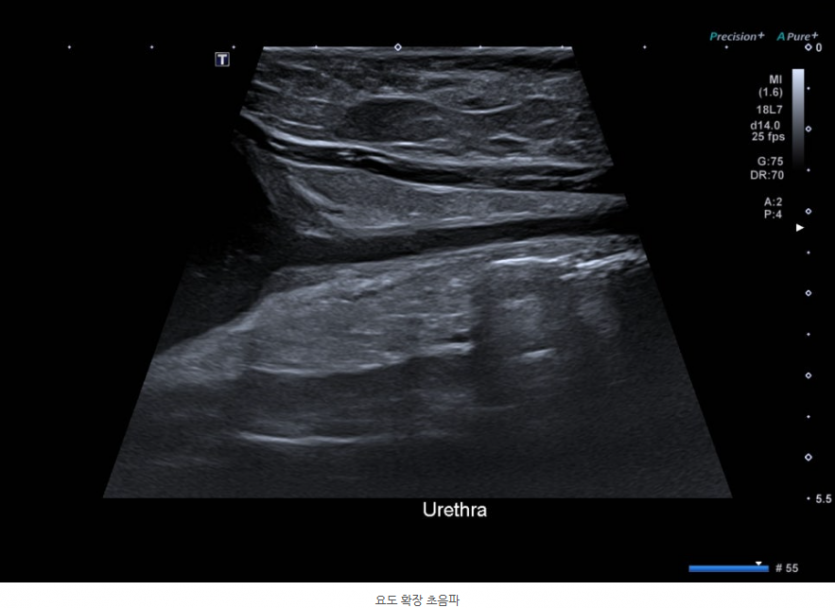

초음파 검사를 통해 방광 내 다량의 슬러지, 요도 확장, 방광 주변부 심한 염증과 소량의 복수, 양쪽 신장 주변 염증소견이 확인되었습니다.